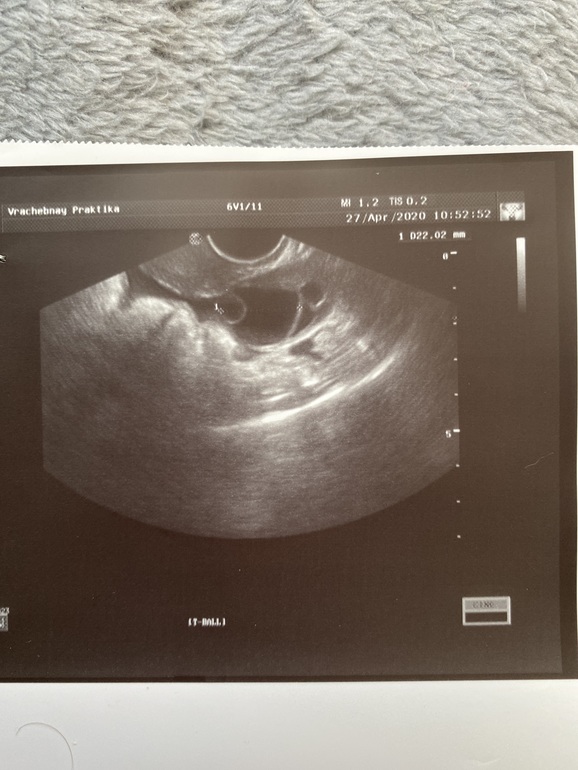

Сегодня (21день) фолликул 22, эндометрий 7,5.почему он стал меньше?овуляции так и нет, но после узи через три часа была капля крови, могла ли это быть овуляция? Фото узи прикрепляю, может кто понимает ,что фолликул готов у выходу, врач ничего не сказала...первое фото 19 день, второе сегодня.

На втором - очень похоже на яйценосный бугорок, поэтому овуляция могла бы быть сразу после УЗИ)

Эндометрий могли просто плохо померить)

Фолик лопается как раз от 20 до 23мм, далтше считается переросток и не лопнет, а либо перерастёт в кисту, либо состарится.